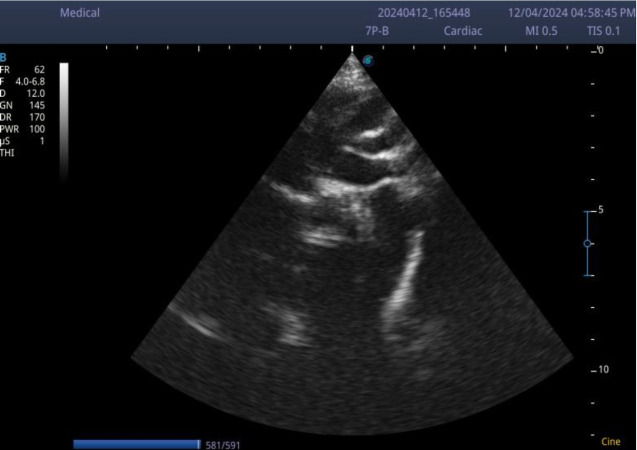

主动脉缩窄是一种梗阻性的先天性心脏缺陷,表现为上肢高血压。如果不及时治疗,主动脉缩窄可导致左心室功能障碍和脑血管病。由于其微妙的表现漏诊是常见的伴随并发症。这是一个病例报告,一个表面上健康的3岁男孩在轻微跌倒后陷入昏迷。他有上肢高血压,下肢脉搏几乎摸不到。脑部计算机断层扫描(CT)显示非外伤性出血性中风,超声心动图显示严重的左心室肥厚和主动脉严重缩窄。主动脉缩窄可表现为慢性上肢高血压患儿并发非外伤性出血性中风。幼儿常规血压测量可作为早期诊断的筛查工具。

Coarctation of the aorta is an obstructive form of congenital heart defects that presents with upper limb hypertension. If untreated, Coarctation of the aorta can lead to left ventricular dysfunction and cerebral vasculopathy. Missed diagnosis due to its subtle presentation is common with attendant complications. This is a case report of an apparently healthy 3-year-old boy who lapsed into a coma after a trivial fall. He had upper limb hypertension and the pulses in the lower limbs were barely palpable. Brain computed tomography (CT) revealed non-traumatic haemorrhagic stroke and echocardiography showed severe left ventricular hypertrophy and severe coarctation of the aorta. Coarctation of the aorta can manifest as chronic upper limb hypertension in children with complicated non-traumatic haemorrhagic stroke. Routine blood pressure measurement in young children can serve as a screening tool for early diagnosis of the condition.